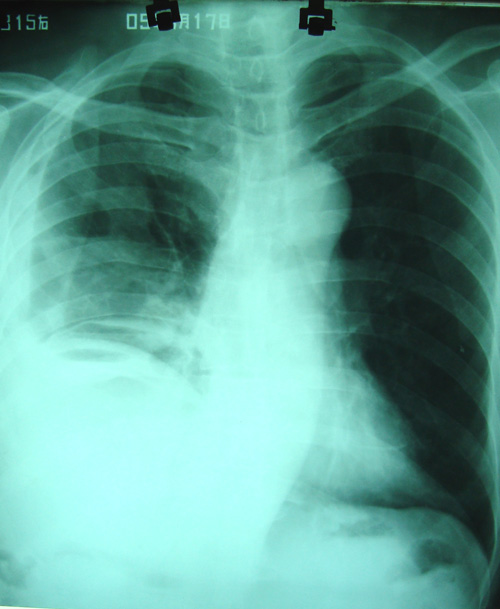

经治疗至17日胸闷痛摄片如9号图,20日复查如7,8号片.

结论:右侧大量胸腔积液,可疑膈下脓肿.